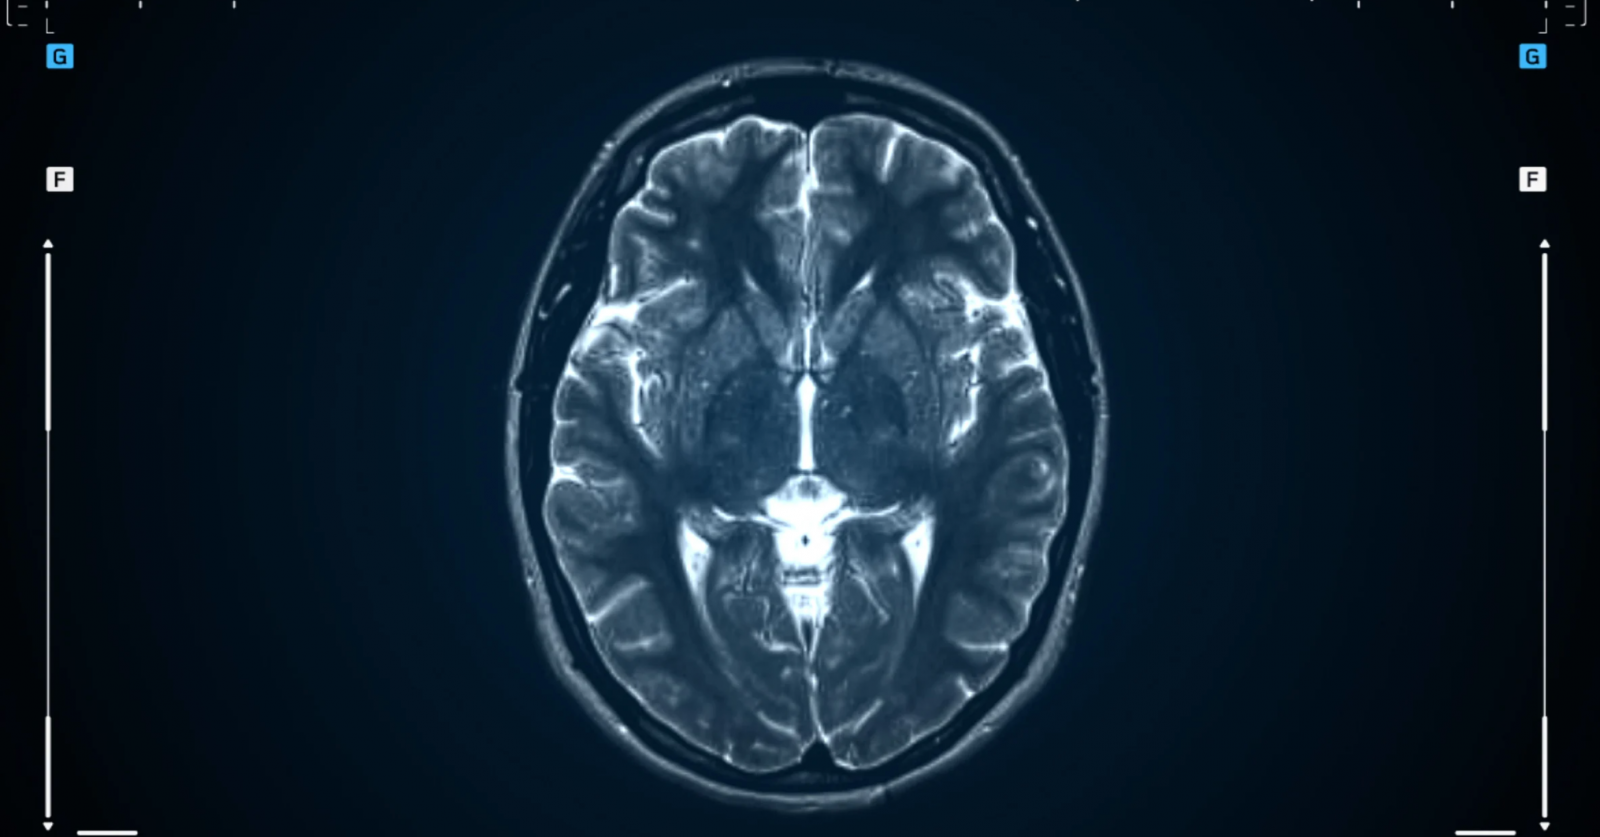

โรคมะเร็งที่พบบ่อยในกลุ่มวัยเรียนและวัยทำงานมีหลายโรค ได้แก่ มะเร็งเม็ดเลือดขาว มะเร็งต่อมน้ำเหลือง มะเร็งกระดูก มะเร็งสมองและระบบประสาท รวมไปถึงโรคมะเร็งที่เกี่ยวข้องกับฮอร์โมน เช่น มะเร็งเต้านม มะเร็งปากมดลูก มะเร็งรังไข่ หรือมะเร็งอัณฑะ